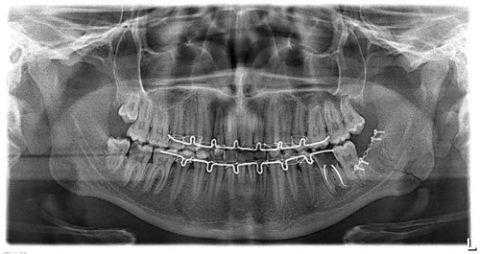

- рентгенограмма в прямой и боковой проекции;

- ортопатомограмма и прицельная рентгенография причинного зуба;

- компьютерная и магнитно-резонансная томография.

Цена проведения диагностики зависит от количества процедур и необходимости осуществления томографических методик исследования костной ткани.

![Ортопатомограмма пациента с травматическим остеомиелитом]()